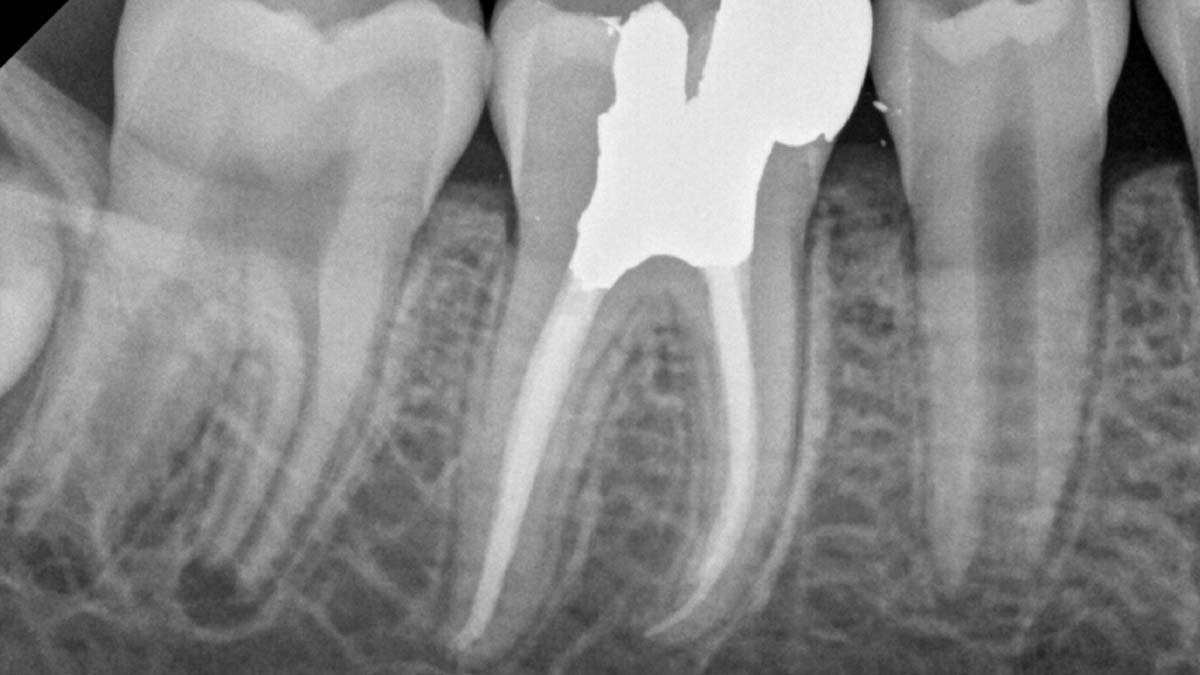

À gauche : l’utilisation de différentes formulations de gutta-percha dans un même cas peut entraîner différents degrés d’opacité.

Avec l’aimable autorisation du Dr Phillip Bell, Mooresville, NC

À droite : Gutta-Smart et Conform Fit utilisent la même gutta-percha avancée pour une cohérence radiographique.

Avec l’aimable autorisation du Dr Nathaniel Behrents, Fayetteville, AR